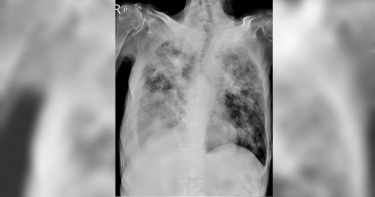

與肺結核症狀相似 「非典型」死亡率卻更高

3月24日是世界結核病日,肺結核曾是國病,難以根治,不過在衛生單位的努力下,發生率已經大幅降低。然而,「非典型結核」非結核分枝桿菌感染症的個案卻逐年上升。有鑑於此,臺中榮總特別成立「分枝桿菌中心」,主任黃偉彰提醒,兩種疾患病狀極為相似且難以區別,但非結核分枝桿菌感染5年死亡率高達35%,民眾太晚就醫恐無法治癒,若出現發燒、咳嗽、咳血、體重減輕等症狀,應及早就醫檢查。一名54歲女性出現咳血狀況求診,診斷為非結核分枝桿菌感染,接受抗生素治療但未改善。經轉診至臺中榮總,進一步進行分枝桿菌培養及分型、藥物敏感性鑑定,接受精準藥物治療,並配合進行外科手術,終於成功控制疾病回到工作崗位。「非典型結核」人數將近肺結核2倍結核病感染源為分枝桿菌屬,分為兩種:第一為結核菌群,就是所謂的「結核病」;第二為非結核分枝桿菌,又稱「非典型結核」。依據疾管署資料顯示,在台灣,結核病的發生率已經從2005年的每10萬人口73例逐年減至2022年的28例。然而非結核分枝桿菌感染個案卻逐年上升,2022年發生率達到每10萬人口50例。症狀相似 「非典型」死亡率卻更高 根據結核菌侵犯的位置,結核病可分為「肺內」結核和「肺外」結核。高風險族群包括支氣管擴張症患者、免疫功能低下者、愛滋病患、長期使用類固醇者、慢性阻塞性肺病患等。建議家中浴室、蓮蓬頭應加強清潔,杜絕細菌藏匿。黃偉彰指出,兩種疾患的共同症狀為發燒、咳嗽、呼吸喘、咳血、體重減輕,而且照X光或電腦斷層掃描也難以區分。唯一的不同處在於治療方式,尤其非結核分枝桿菌感染需使用至少3種抗生素,不僅容易出現副作用,若患者同時服用高血壓或糖尿病等慢性病藥物,也容易有藥物交互作用,加上使用的抗生素抗藥性高,因此可供選擇的藥物較少,導致治療難度與死亡率皆更高。無論是「結核病」或「非典型結核」,從診斷到治療都相當複雜,需要多專科的協助處理,才能達到全面的照顧。醫師呼籲民眾若無法確診哪一疾患,建議進一步就醫進行分枝桿菌鑑定、抗藥性藥物檢測,精準治療可提高治癒率。「非典型結核」如何精準治療?點這裡